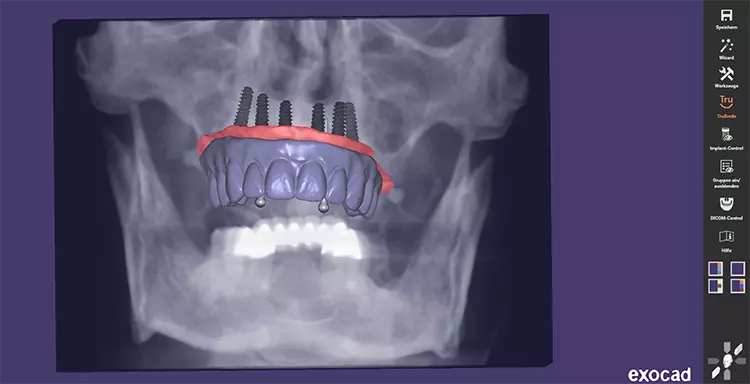

Hierzu wurde eine digitale Planung des Zahnersatzes im Sinne eines Backward Planning erstellt (Abbildung 3 und 4). Nachdem eine digitale Volumentomographie (DVT) des Patienten mit dem vorhandenen Zahnersatz in Okklusion inklusive Referenzpunkten und zusätzlich eine DVT der Prothese extraoral durchgeführt wurde, konnten im Anschluss mit dem Programm Exoplan® beide Scans gematcht werden. Auf dieser Grundlage wurden die sechs Implantate virtuell in idealer Position unter Berücksichtigung des ortsständigen Knochens geplant.

Die Vermeidung einer Sinusbodenelevation, sowie ein maximal großes Unterstützungspolygon standen im Fokus der präoperativen Planung für die festsitzende prothetische Versorgung. Dabei ergab sich ein 17 bzw. 30 Grad Neigungswinkel der distalen Implantate, der durch die Mesostruktur der Multi-unit Abutments ausgeglichen werden sollte, um eine gemeinsame Einschubrichtung für die geplante provisorische Brückenversorgung zu ermöglichen.